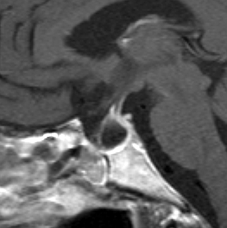

MRI画像(T1低信号のもの)

ラトケ嚢胞のMRIです。両耳側半盲という視野の障害(目がみづらい)で発症した女性のものです。左はT2強調画像と言います。右はガドリニウム造影剤を使ったものです。嚢胞のうすい壁だけが見えますが,中身は液体です。鼻孔から入って嚢胞をぷつんとつぶすだけの手術をします。薄い黄色の水のような液体が出ました。

手術後のMRIです。嚢胞はぺしゃんこになって視力は良くなりました。正常の下垂体は残っていてホルモンの障害もありません。